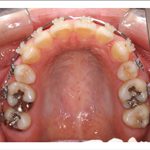

1) 矯正前の状態

叢生(そうせい…歯がデコボコしたり、重なりあって生えていたりする状態)

開咬(かいこう…奥歯はしっかり噛んでいるが、上下の前歯が噛まずに隙間がある状態)